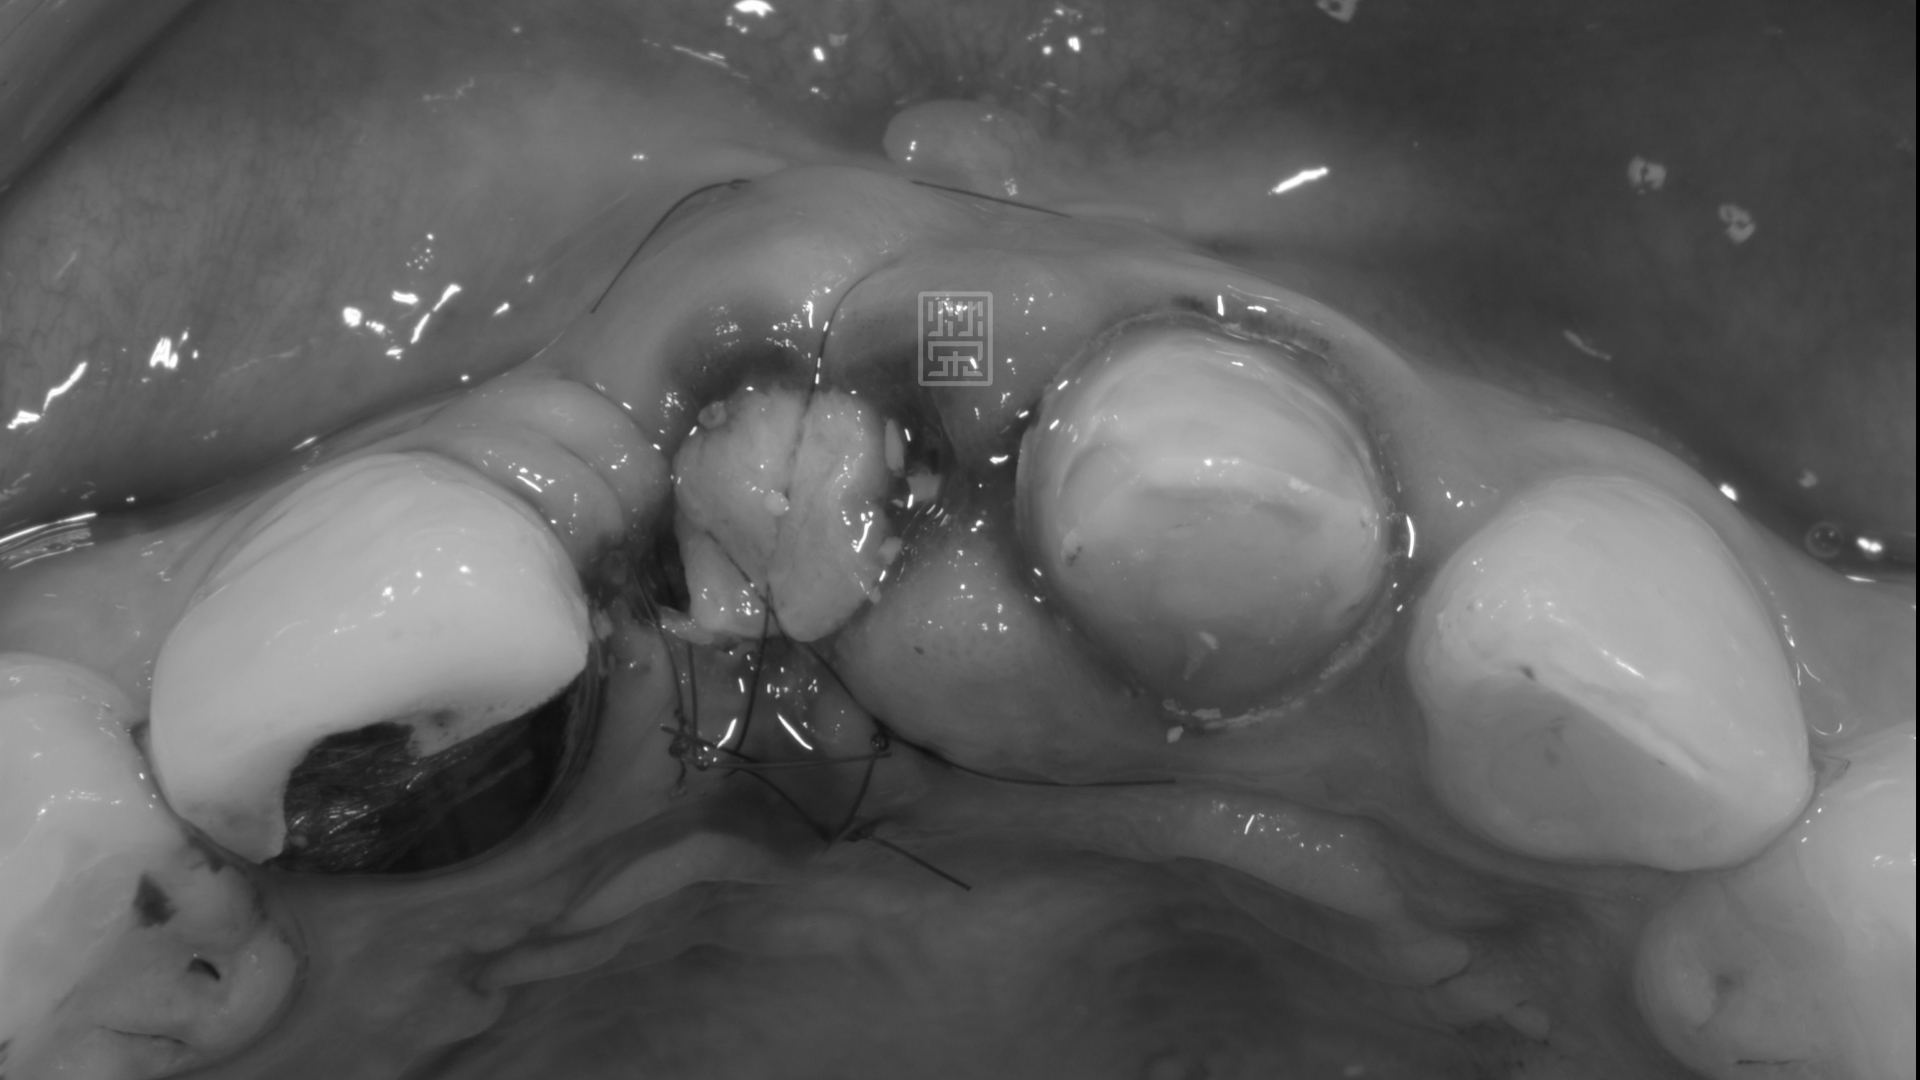

植牙手術合併牙齦轉移